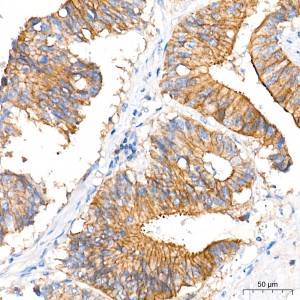

| Immunohistochemistry analysis of paraffin-embedded Human colon carcinoma tissue using [KD Validated] MCT1 Rabbit mAb (A27270) at a dilution of 1:600 (40x lens). High pressure antigen retrieval performed with 0.01M Tris-EDTA Buffer (pH 9.0) prior to IHC staining. |